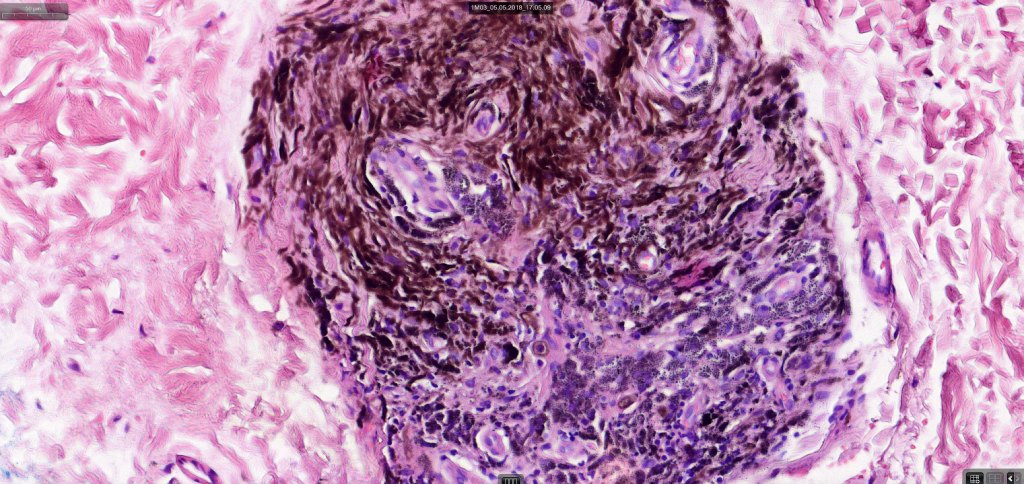

Histologically, it is characterized by a dense population of spindled, dendritic melnanocytes & melanophages with variable fibrosis. It may sometimes represent a component of a combined nevus. Mitotic activity is not usually present and pleomorphism is absent (see atypical blue nevus below). Involvement of the arrector pili muscle is not uncommon.

Cellular blue nevus

Histological features

•Most characteristic is the dumbbell silhouette although a plague morphology may also be encountered

•Admixture of spindle cells, pigmented bipolar or dendritic cells & melanophages

•Cytoplasm is pale and nuclei are small with inconspicuous nucleoli

•An alveolar pattern is characteristic particularly with clear cell nodules

•Multinucleate giant cells sometimes present

•Stromal fibrosis, myxoid change, vascular hyalinization with cyst formation are often seen